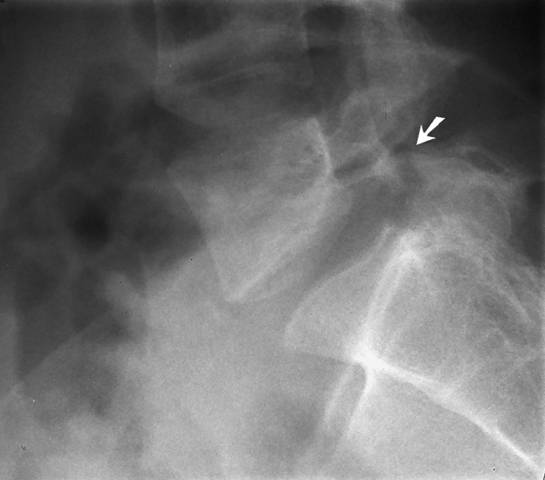

Spondylolysis and Spondylolisthesis of the L5 Vertebra

Spondylolysis and spondylolisthesis of the L5 vertebra. Spondylolysis (arrow) and mild spondylolisthesis of the L5 vertebra